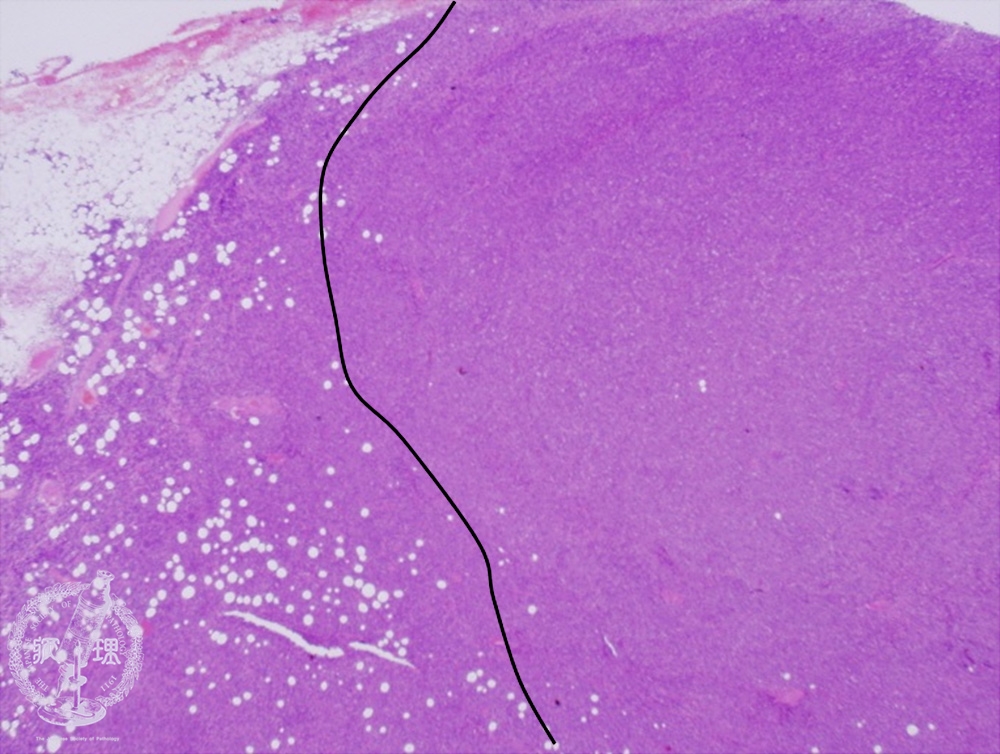

- ★(6)Diffuse large B-cell lymphoma

Microscopic image (H&E low power view): Atypical, proliferating lymphocytes are seen breaching the lymph node capsule and infiltrating into the surrounding tissue (outside of the line on left). At low power magnification, no residual follicles are observed.